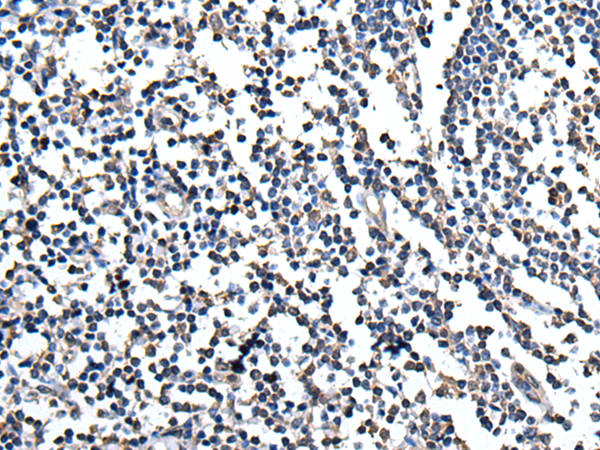

分类: 科研抗体货号: P08634别名: CMM10; HPOT1应用: IHC反应种属: Human